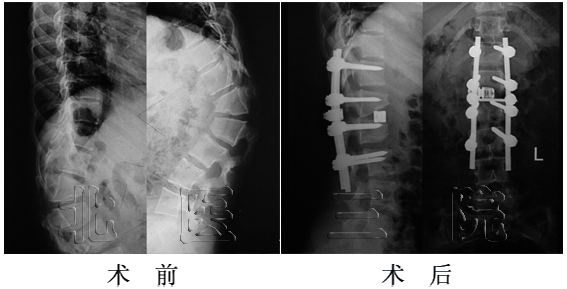

女性,14岁, L5重度发育不良性滑脱(ⅴ°),行前后联合入路L5椎切除、S1上终板截骨、L4-S1固定融合术。